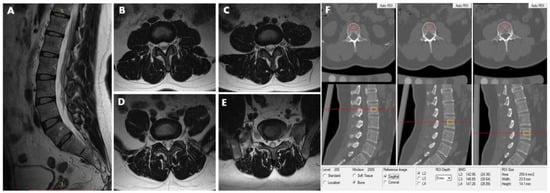

2.5. Lumbar Scanning by MRI

2.6. Definition of Lumbar Intervertebral Disc Herniation